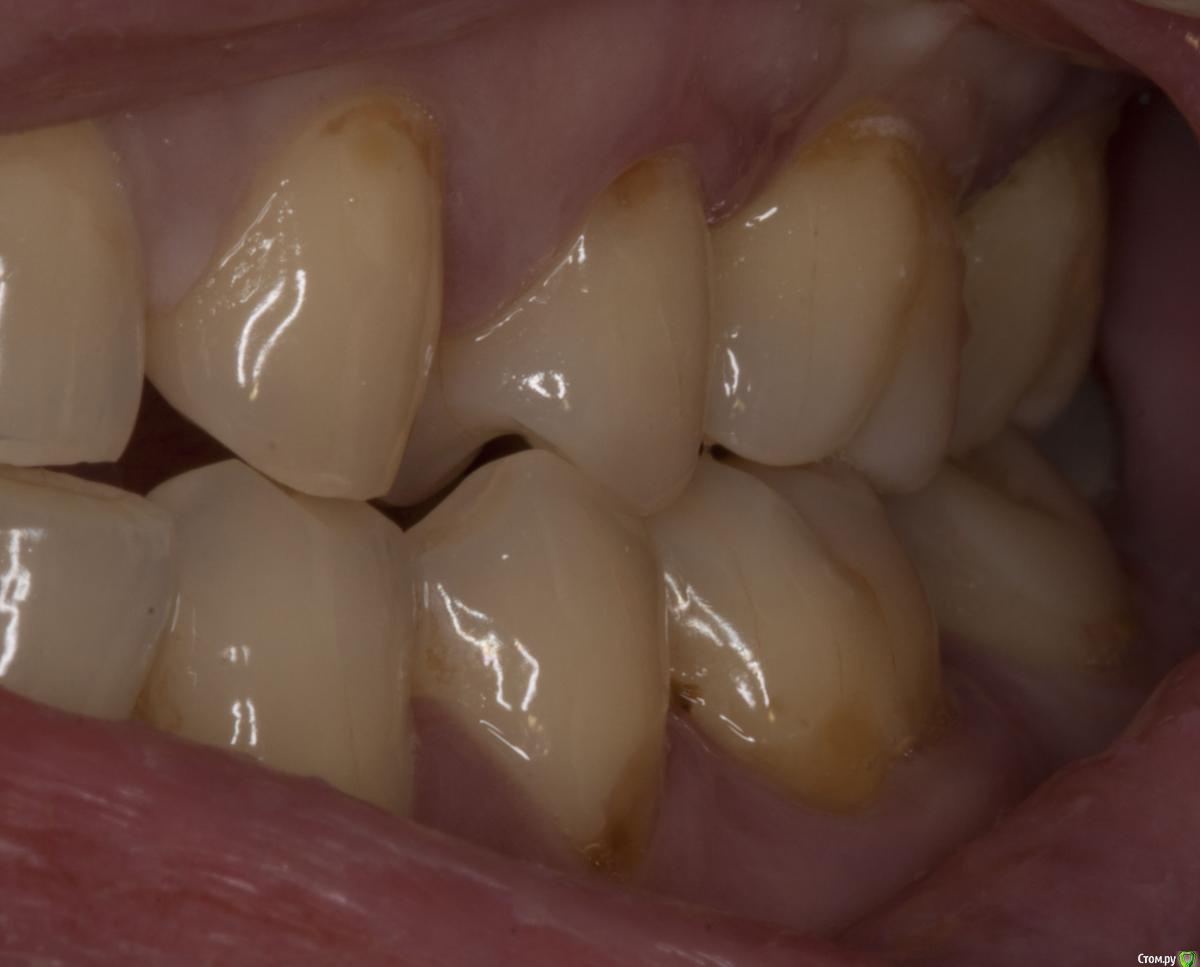

Sampson Опубликовано 29 июля, 2015 Поделиться Опубликовано 29 июля, 2015 (изменено) Зуб на удаление и диагностическое вскрытие. Пациент к ЛОРуФото зуба хочется увидеть. Пульпит может быть следствием пародонтита из-за оголения боковых ответвлений. Изменено 29 июля, 2015 пользователем Sampson Ссылка на комментарий

M@estro Опубликовано 29 июля, 2015 Поделиться Опубликовано 29 июля, 2015 (изменено) Травматический узел. Изменено 29 июля, 2015 пользователем M@estro 10 Ссылка на комментарий

M@estro Опубликовано 30 июля, 2015 Поделиться Опубликовано 30 июля, 2015 Паш, расскажи подробнее пожалуйста Пришла пациентка на прием, болит зуп. Сделали снимок , карман локально до 1 см глубиной. Подвижность 3 степени, обострение. Зуб целый. Ну челюстью подвигала - оппа! - вот и привет. Причем призналась. что сресяк у нее месяца 4 -5 усилился, вот и окончательно не выдержал. Вторая была девушка - тоже 2.6 зуб, но я не фотал её. Ситуация похожая, я тоже зуб вынул просто. Там вообще был целый моляр, ни дырочки в нем, ни пломбы. Год лечили от гайморита антибиотиками её лоры, потому как " все зубы интактные" . В поликлише в смотровом проглядели её этот зуб. Я удалил - через две недели пришла на приём с благодарностью - разложило нос ) Видел недавно её - гайморита нет и следа. Ссылка на комментарий

bogdan_r Опубликовано 30 июля, 2015 Поделиться Опубликовано 30 июля, 2015 но у вашем случае у антагониста пломба, а у паца тс нет пломбы на антагонисте. или там другая причина супраоклюзии? Ссылка на комментарий

M@estro Опубликовано 3 августа, 2015 Поделиться Опубликовано 3 августа, 2015 но у вашем случае у антагониста пломба, а у паца тс нет пломбы на антагонисте. или там другая причина супраоклюзии? Я специально сделал серию фото, чтобы виден был перегруз 2.6 при левой латеротрузии. Ссылка на комментарий